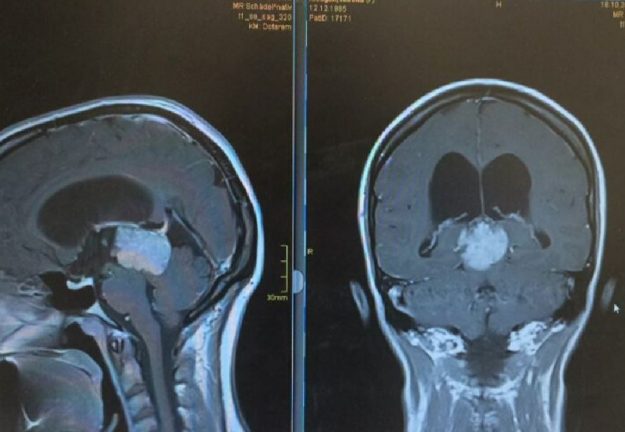

Αραχνοειδής Κύστη Εγκεφάλου

Ασθενής γυναίκα 58 ετών με πονοκεφάλους και διαταραχές όρασης. Ο οφθαλμολογικός έλεγχος έδειξε οίδημα οπτικών θηλών άμφω και σημαντικό περιορισμό των οπτικών πεδίων. Τα συμπτώματα της ασθενούς ήταν προοδευτικά επιδεινούμενα, το ίδιο και οι εξετάσεις της. Η μαγνητική εγκεφάλου ανέδειξε ευμεγέθη αραχνοειδή κύστη δεξιά κροταφικά με σημαντική πίεση επί του υγιούς εγκεφάλου και παρεκτόπιση των…